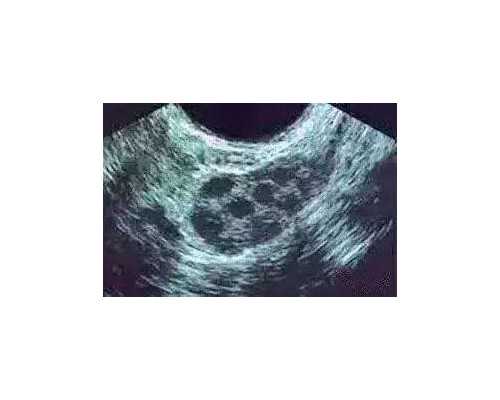

上海试管助孕中心的基本收费项目在上海,试管助孕中心的基本收费项目包括体外受精、胚胎移植和冷冻胚胎保存等。根据不同机构和服务质量,收费标准也有所不同。据统计,在上海市区一般的试管助孕中心,IVF收费在1.5万元到3万元之间;胚胎移植收费在1万元到2万元之间;冷冻胚胎保存每年大约需要花费5000元左右。

8、IVF-ET主要包括促排卵取卵、体外受精、胚胎移植等过程。